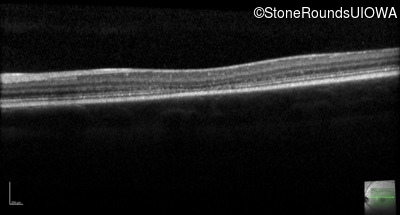

Optical Coherence Tomography - Right - 20/100 -1

Exemplar / OCT Stack